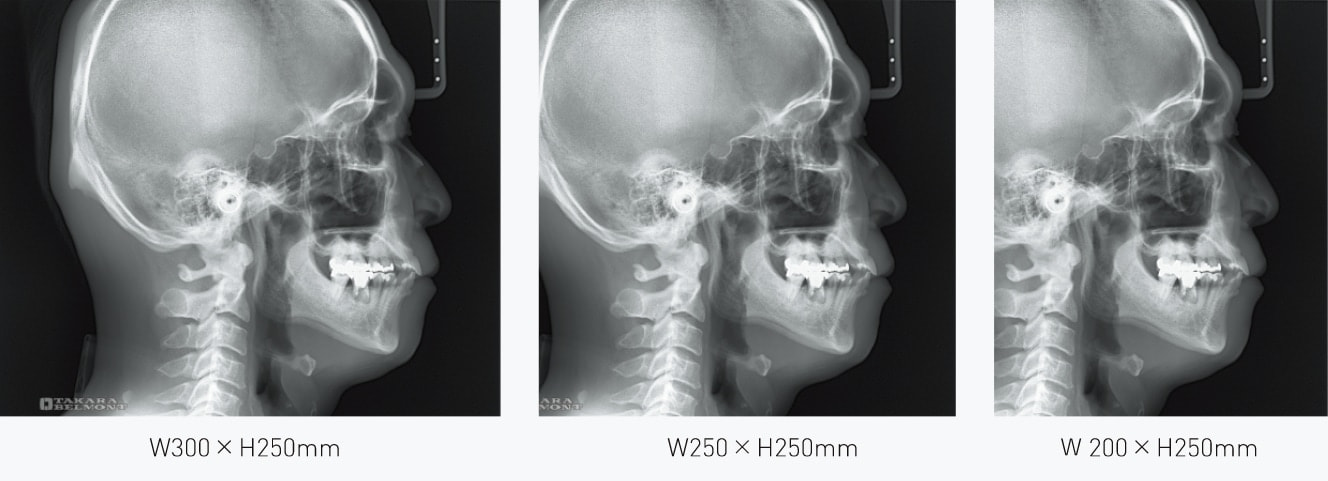

撮影モード

LA撮影モード

六切りサイズ(W254×H203mm)より一回り大きい、最大W300×H250mmを含む3つの撮影エリアから選択できます。

撮影仕様:セファロ

| 項目 | 内容 |

|---|---|

| 撮影部位 | 側面(LA)、正面(PA)、手根骨 |

| 撮影範囲 | W200×H250㎜ 〜 W300×H250㎜ |

| 撮影時間 | 0.5秒 |